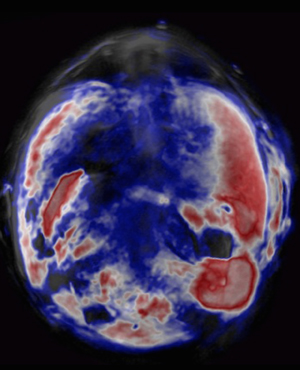

A chemical probe that selectively and safely illuminates tumor cells can significantly boost the capabilities of an alternative bioimaging technique (red; concentration of probe one hour after injection).

After testing different photosensitizers, the team selected a promising substance known as zinc phthalocyanine (ZnPc) to inject into living mice with tumors. Experiments confirmed their hypothesis: the photosensitizers produced strong photoacoustic signals as they passed through vital organs and zeroed in on the tumor cells. Within ten minutes of injection, signals from the ZnPc contrast agents illuminated the precise position of diseased tissue (see image). The ZnPc cleared harmlessly from the mice within one day, resulting in a low overall toxicity.